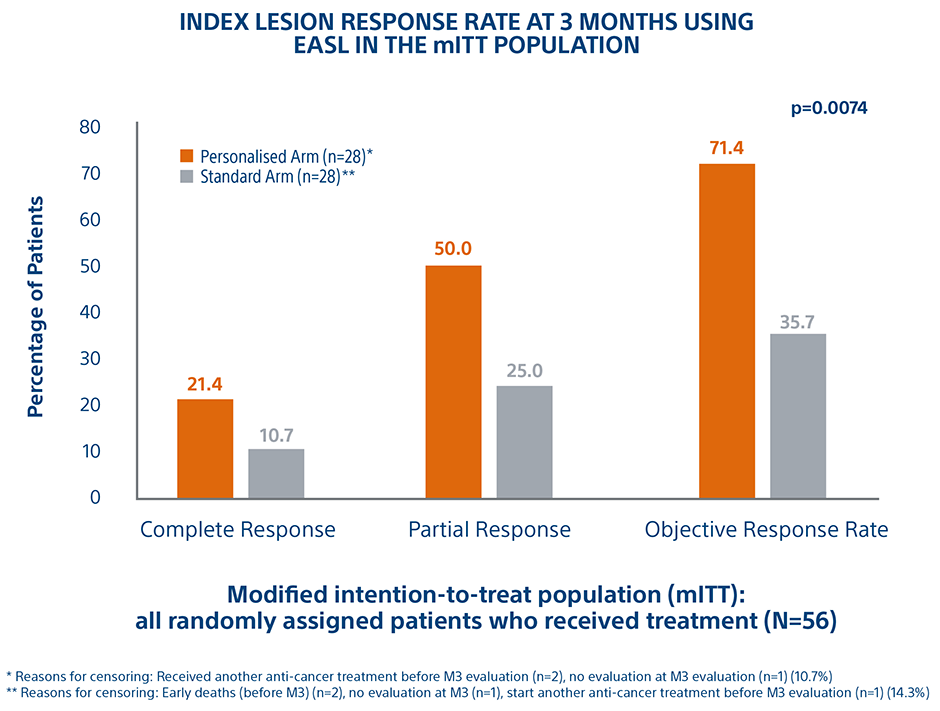

Personalized Dosimetry Improves Response